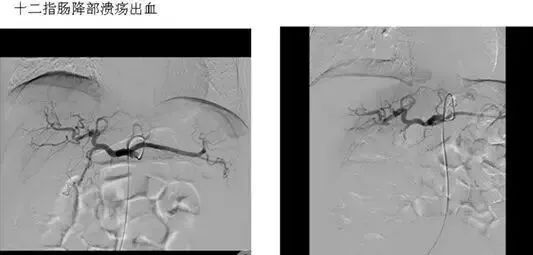

五、出血性疾病:鼻腔大出血、咯血、上消化道大出血、经皮肾镜术后出血、膀胱出血、产后出血等

经原血管造影的导管或特制的导管,将栓塞物送至靶血管内,一是治疗内出血如外伤性脏器出血、溃疡病、肿瘤或原因未明的脏器出血。另一是用栓塞法治疗肿瘤,因肿瘤循环部分或全部被栓塞物阻断,以达控制肿瘤之生长,或作为手术切除的一种治疗手段;亦可用于非手术脏器切除,例如注射栓塞物质于脾动脉分支内,即部分性脾栓塞,以治疗脾功亢进,同时不影响脾脏的免疫功能。